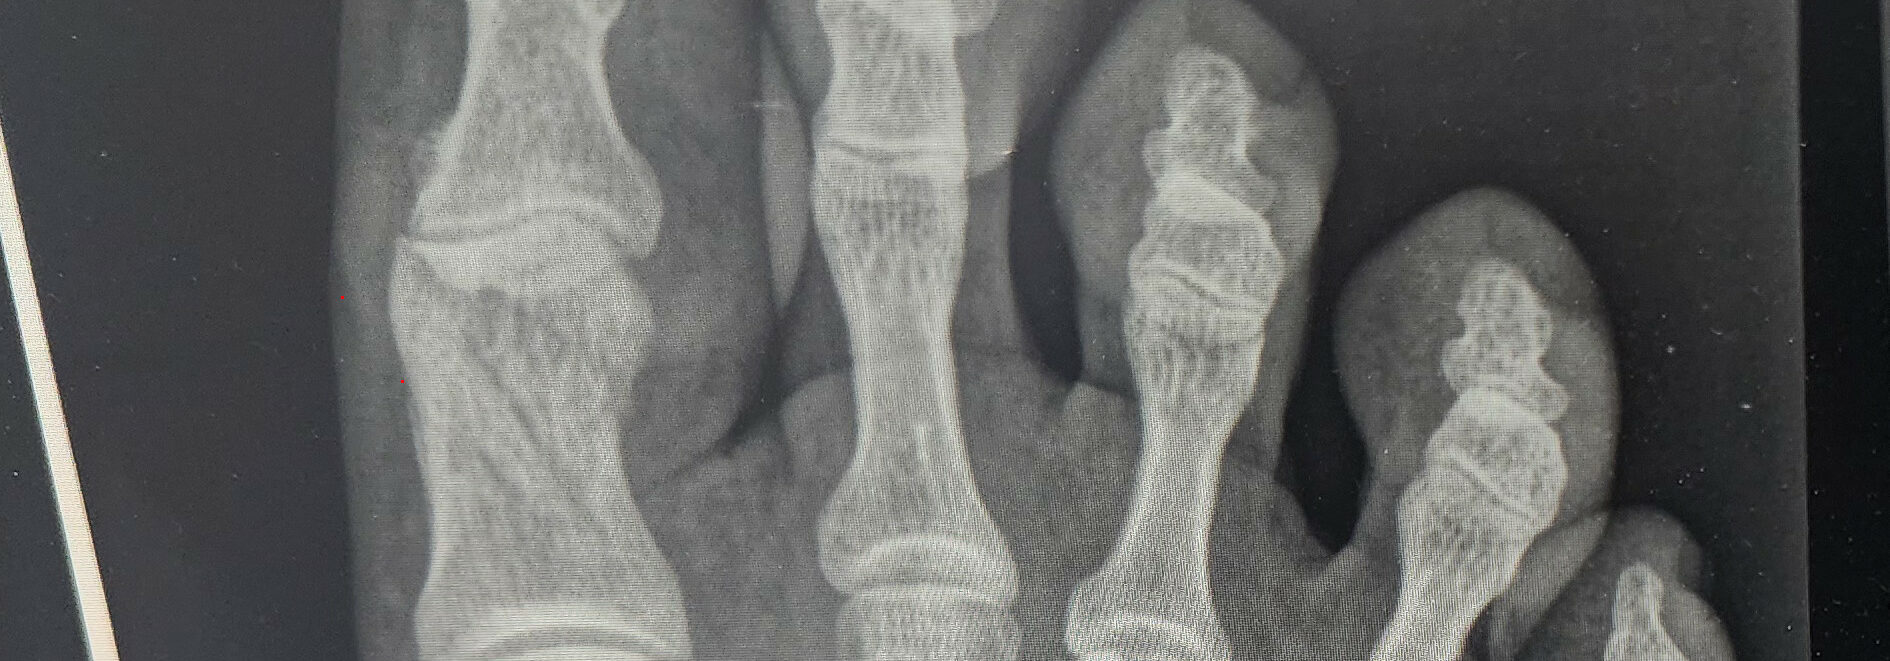

The doctor saw me at 9 am promptly. He immediately takes X-rays, and after a few minutes, I hear from the other room, ‘NICE’! It is never good when a doctor says that. The aftermath was four fractures in the right big toe in an x pattern. My Wolverine-esque, aka big bones, is why things barely held together instead of completely shattering. I would have a 6-8 week recovery period before I could start using the toe again. Effectively, pressing pause on my race season.